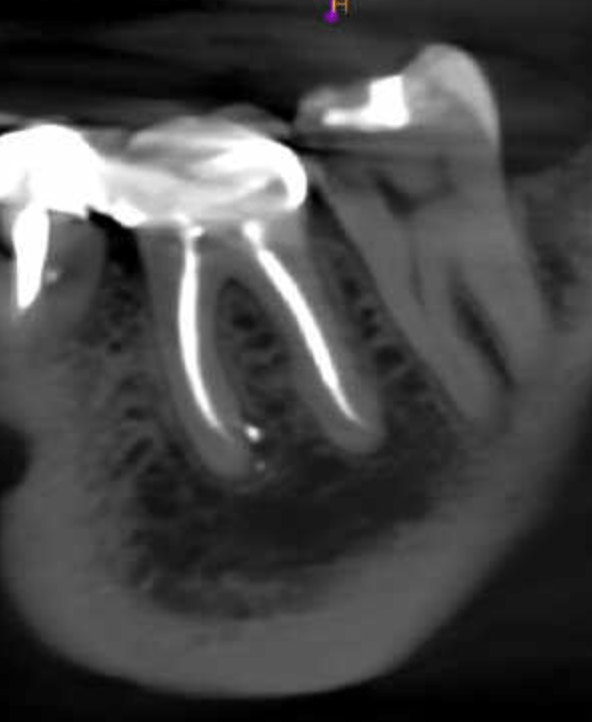

Molar inferior, conducto CM